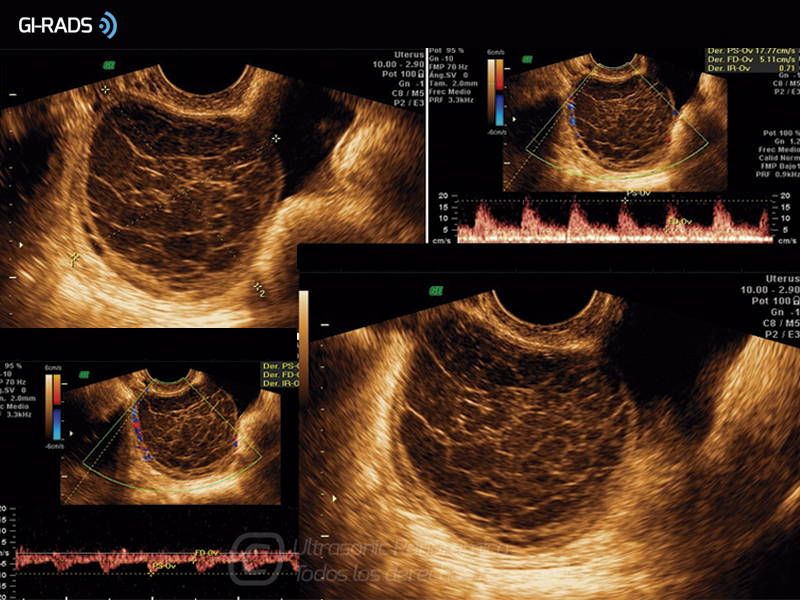

Patologías Benignas – Cuerpo Lúteo Hemorrágico

• Patologías Benignas – Cuerpo Lúteo Hemorrágico